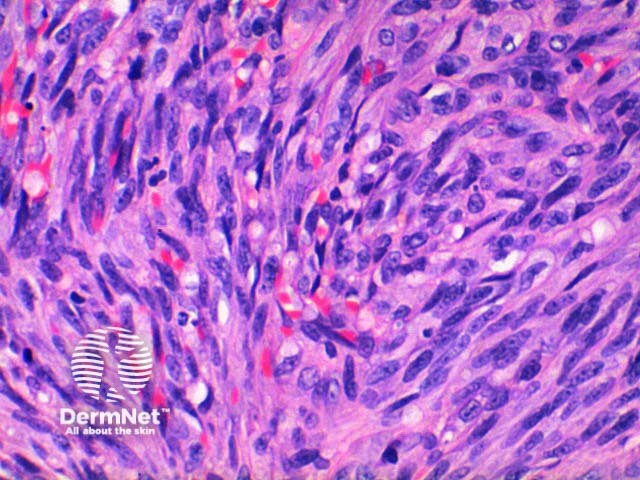

The low power view of the histology of Kaposi sarcoma is of a cellular dermal nodule (Figure 1). There may be varying degrees of overlying epidermal changes which can range from prominent hyperkeratosis and acanthosis to frank ulceration. The dermal proliferation is comprised of a spindle cell proliferation of endothelial cells forming sinuous vascular spaces. These may be sparse in patch phase lesions, progressing to fascicles of spindle cells in nodular lesions (Figures 2,3). This fascicular pattern has been likened to schools of fish. The spindle cells infiltrate through the collagen, forming slit-like spaces, especially towards the periphery of the lesions (Figure 4). Where the newly formed vessels project into an existing space the promontory sign is seen (Figure 5). This is now recognised as not being specific to this condition.

In plaque and nodular stage lesions, there may be visible intracellular and extracellular hyaline globules, though to represent engulphed erythrocytes. While rare this may be seen in patch stage lesions. They stain PAS positive. While the endothelial proliferation is frequently monomorphic, there may be significant nuclear atypia with increased mitotic activity (Figure 6). When prominent atypia is seen the tumour fits into the category of an anaplastic variant.

Figure 2

Figure 3